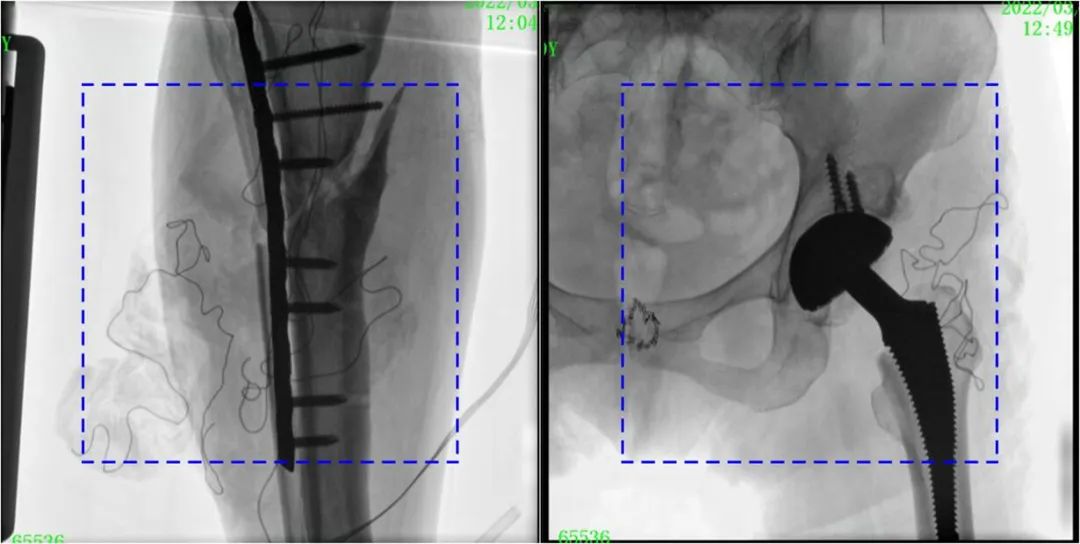

術中定位準確、出血量少,術后影像顯示股骨移位糾正,恢復良好力線,手術效果良好。

PLX119C臨床圖像與傳統圖像對比

注:藍色虛線內為傳統21CM×21CM平板的成像區域。